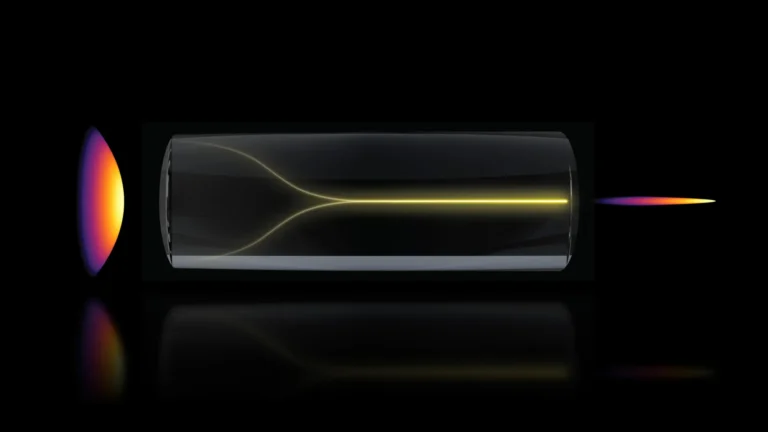

The scientific endeavor, detailed in the latest issue of the Journal of Sport and Health Science, set out to determine if the adoption of a regular aerobic exercise routine could either decelerate or even reverse the progression of what researchers term "brain age." This concept is assessed through sophisticated magnetic resonance imaging (MRI) techniques, which provide an estimation of a brain’s apparent age relative to an individual’s chronological age. A disparity indicating an older brain, quantified as a higher brain-predicted age difference (brain-PAD), has been previously associated with diminished physical and cognitive capabilities, as well as an elevated mortality risk. Dr. Lu Wan, the lead author and a data scientist at the AdventHealth Research Institute, highlighted the significance of the findings, stating, "We discovered that a straightforward exercise program, aligned with current health recommendations, can result in a discernible reduction in brain age within a mere twelve months." She further elaborated on the implications for public health, noting, "Many individuals harbor concerns regarding the preservation of their brain health as they advance in years. Studies like this provide encouraging insights rooted in accessible, everyday behaviors. While the absolute magnitude of these changes may appear modest, even a one-year shift in brain age can accrue substantial benefits over the span of several decades."